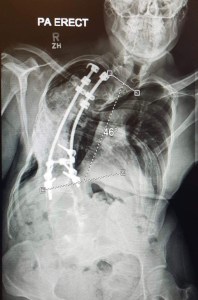

I shrugged this off at first as I already knew I had a restricted lung capacity because of the scoliosis. But there was a seed of worry at the back of my mind which eventually lead me to getting referred back to the hospital where I had my spinal fusion all those years ago.

As is often the case when revisiting a place from childhood, the hospital at Stanmore seemed much smaller than I remembered. I was surprised I still knew the way to the X-ray department. Countless walks though those cold corridors with their awkward slanting floors that resembled a poorly drawn Escher painting had been forever etched onto my brain.

It turned out that nothing structurally had changed with my spine, but I was referred to another hospital in London for lung function tests and a sleep study.